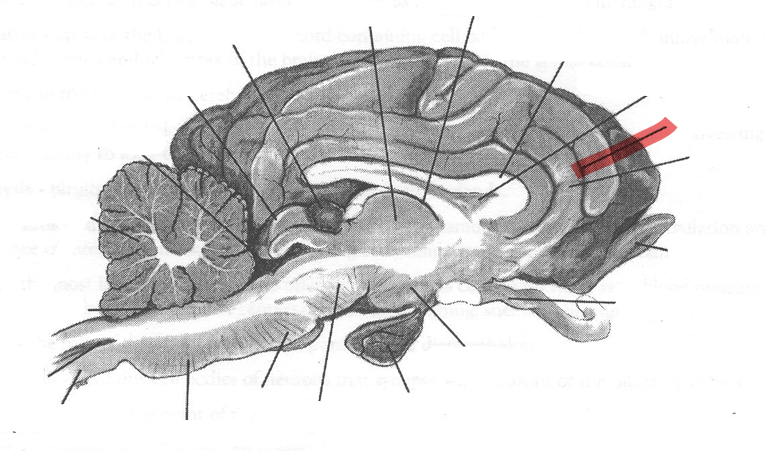

Identify highlighted arrow

Spinal cord